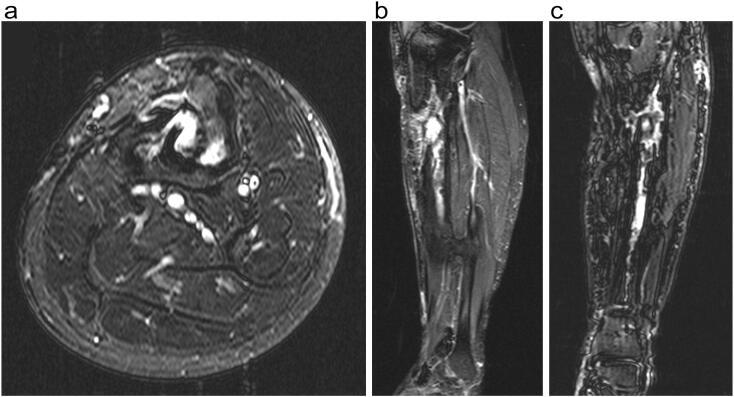

Gram-positive organisms are known causative agents in toxic shock syndrome (TSS), an acute disease caused by bacterial exotoxins. During routine instrumentation removal for chronic osteomyelitis, intraoperative debridement, reaming, and irrigation can lead to cell lysis and subsequent dissemination of the bacterium exotoxin, which can result in acute cardiovascular compromise. We present two cases of chronic osteomyelitis in healed long-bone fractures that were treated with deep instrumentation removal and surgical debridement using a reamer-irrigator-aspirator (RIA) system. Both patients had positive wound cultures and both developed acute intraoperative hypotension during the reaming/irrigation portion of the procedure. Case 1 experienced cardiac arrest and was resuscitated for several days in the ICU. Case 2 underwent intra-operative hypotension and was resuscitated appropriately. The RIA or standard reaming systems must be used with caution during debridement of osteomyelitis in the presence of known toxin producing bacteria. The risk of iatrogenic spread of infection or extravasation of intramedullary contents is present; a high index of suspicion with any change in vital signs and prompt response can help mitigate the effect of adverse outcomes associated with acute and severe intraoperative hypotension.

革兰氏阳性菌是中毒性休克综合征(TSS)的已知病原体,TSS是一种由细菌外毒素引起的急性疾病。在因慢性骨髓炎进行常规器械取出术时,术中清创、扩髓和冲洗可导致细胞溶解以及随后细菌外毒素的播散,这可能导致急性心血管功能障碍。我们报告两例愈合的长骨骨折合并慢性骨髓炎的病例,这些病例采用扩髓-冲洗-吸引(RIA)系统进行深部器械取出和外科清创治疗。两名患者伤口培养均为阳性,且在手术的扩髓/冲洗阶段均出现急性术中低血压。病例1发生心脏骤停,在重症监护病房(ICU)复苏了数天。病例2术中出现低血压并得到了适当复苏。在存在已知产毒素细菌的情况下,对骨髓炎进行清创时,必须谨慎使用RIA或标准扩髓系统。存在医源性感染传播或髓内内容物外渗的风险;对生命体征的任何变化保持高度怀疑并迅速做出反应,有助于减轻与急性和严重术中低血压相关的不良后果的影响。